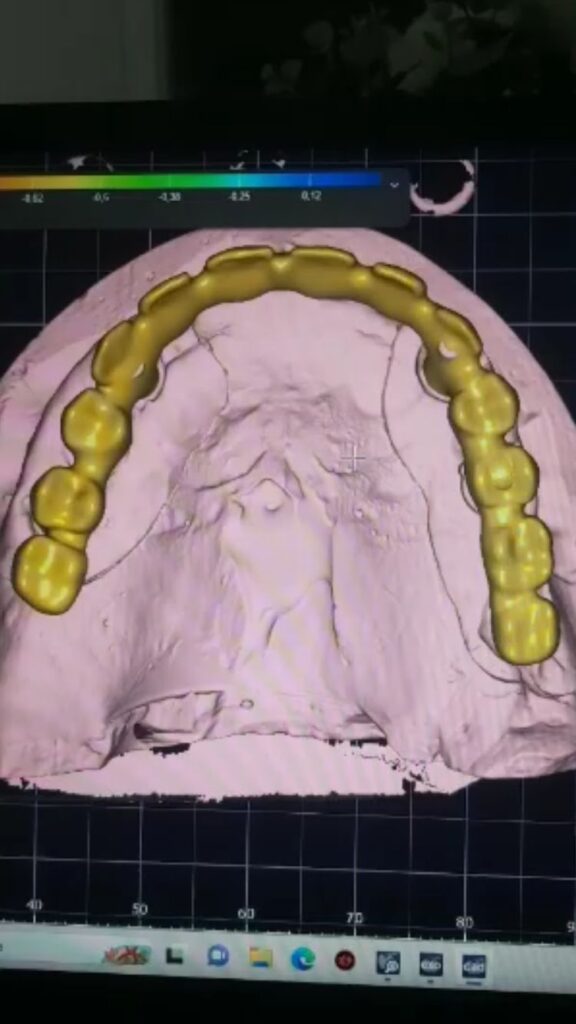

IMPLANT USTU ZIRKONYUM

IMPLANT USTU ZIRKONYUM ALT YAPI

MONOLITIK IMPLANT USTU ZIRKONYUM & ÜSTTEN ViDALI ZİRKONiUM

MULTILAYER IMPLANT ÜSTÜ ZIRKONYUM & ÜSTTEN VİDALI ZIRKONYUM